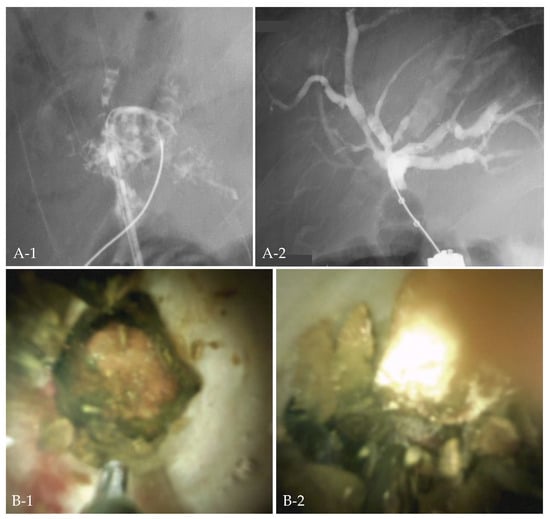

2.3. Case 1: EHL under POCS with Normal Anatomy